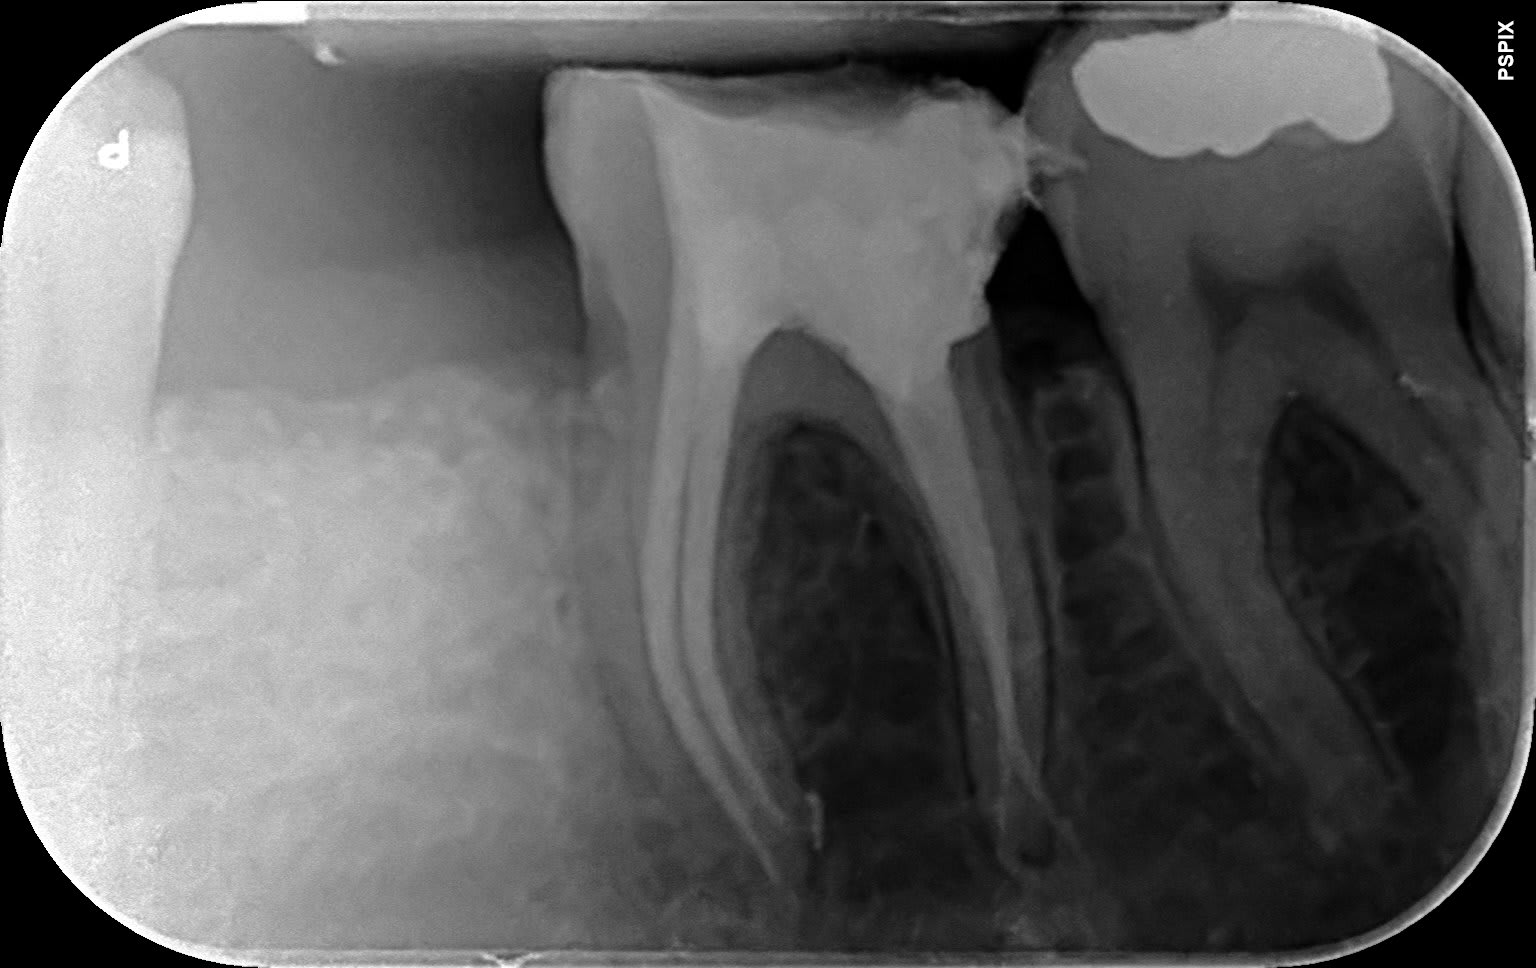

bifide.

Elle est réellement bifide? Sur la radio, elle donne bien l'impression de deux canaux en 8, éventuellement avec une large entrée commune.

Deux canaux fusionnés avec séparation avant l'apex comme le montre la radio. C'est aux protapers golds sans instrumentation manuelle.

Tiens tu le crois ça ? Une 26 bifide. Du jamais vu.